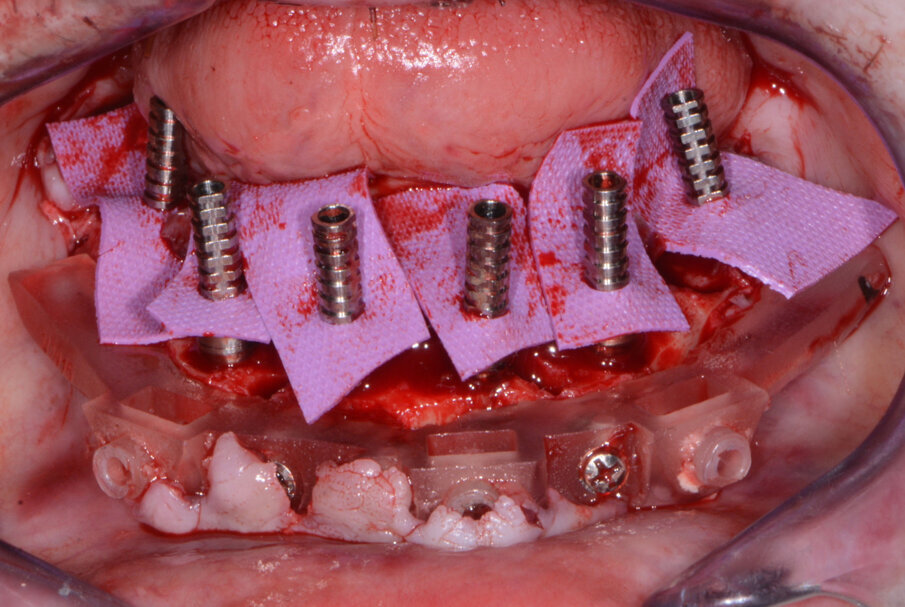

Once the virtual plan had been orchestrated and fully confirmed, the next appointment was for the planned surgery with all the necessary components for the guided surgical approach. The patient was appropriately sedated with intravenous medications, and local anaesthesia was administered in both arches. The tissue was then reflected using the Reflector instrument (GoldenDent) so that the bone levelling surgical guide would be fully seated and fixed with its respective retention screws (Fig. 7). After the positioning of the surgical guide, the maxillary teeth were atraumatically extracted utilising the Physics Forceps (GoldenDent). Once the appropriate bone levelling had been accomplished with the surgical handpiece, the implant surgical guide (Fig. 8) was positioned into the bone levelling guide and the osteotomies for the implants were initiated with a designated pilot drill in the implant system’s guided surgery drill kit (Adin Dental Implant Systems; Fig. 9). Using precise orientation, depth and direction, the guided surgery kit provides fast, effective and predictable preparation and placement of dental implants for dental practitioners. It also features easy-to-follow layouts along containing self-centring drills with built-in stoppers. The unique design of the guide, employing ActiveFlow irrigation technology, directs cooling saline through the guide, ensuring that irrigation reaches the bone and thereby reducing the possibility of bone heating throughout the procedure.

Utilising the Mont Blanc surgical handpiece and AEU 7000 surgical motor (both Aseptico) at a speed of 800 rpm with copious amounts of sterile saline, sequential drill preparation was initiated. Once the osteotomies were complete, the drivers in the guided kit (Adin Dental Implant Systems; Fig. 10) were used to place the dental implants with precise timing so that the flat portion of the internal hex was positioned ideally for receiving the multiunit abutments.

A baseline implant stability quotient (ISQ) reading was taken of these implants utilising the Penguin RFA unit (Aseptico). Since the initial readings were all above 70 ISQ, and the quality of bone after levelling was good, multi-unit abutments (Adin Dental Implant Systems) were tightened into the Touareg-OS dental implants to 30 Ncm, followed by temporary cylinders to 15 Ncm.

Any residual areas around the implants or in the sockets were grafted with a mineralised and demineralised cortical bone grafting material (GoldenDent) to optimise the area for regeneration.

The prefabricated immediate provisional arch restorations with pre-drilled access openings were inspected before being tried in.

The maxillary provisional restoration was tried in to verify a passive fit over the temporary abutments. Once fit had been confirmed, trimmed dental dam pieces were placed to avoid the restoration (Fig. 11) from locking on during the relining procedure with REBASE III FAST set hard reline material (Tokuyama Dental). After the material had polymerised, the immediate provisional restoration was removed and any access material was removed with the Torque Plus laboratory handpiece (Aseptico) and an acrylic bur (Komet). The same procedures were accomplished in the mandibular arch (Figs. 12–14). Once trimmed and polished, the provisional restorations were seated and tightened with a torque wrench at 15 Ncm (Fig. 15). The access openings were filled in three-quarters of the way with Teflon tape, followed by Cavit filling material (3M ESPE). A postoperative panoramic radiograph was taken immediately after the surgery (Fig. 16).